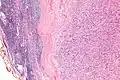

| Micrograph of an intranodal palisaded myofibroblastoma. H&E stain. | |

IPMs are diagnosed by examination of the tissue by a pathologist. They have a rim of peripheral lymphoid tissue (remnant of a lymph node) and consist of spindle cells with nuclear palisading. Red blood cell extravasation is common and blood vessels surrounded by collagen with (fine) peripheral spokes (amianthoid fibers) are usually seen.[2]

Immunostains for smooth muscle actin and cyclin D1 are characteristically positive. The main histologic differential diagnosis is schwannoma.